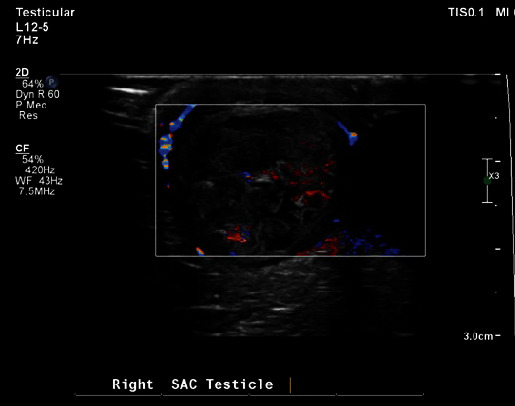

Neonatal testicular torsion (NTT) is a rare but significant condition occurring within the first 30-day postbirth, leading to vascular compromise and potential testicular loss. This paper presents a case of NTT detected incidentally in a neonate with bilateral hydrocele, emphasizing the challenge of early diagnosis and management complexities. The infant underwent surgical intervention involving detorsion and bilateral orchiopexy but eventually required right orchiectomy due to necrosis. The paper highlights the prevalence of NTT in conjunction with hydrocele and stresses the importance of parent education and vigilant follow-up. Various diagnostic methods, primarily ultrasonography, and a range of management strategies are discussed, considering factors such as salvage potential, risk to the contralateral testicle, and surgical intervention's risks and benefits. The paper argues for individualized management, taking into account specific neonate conditions and parental preferences, underlining the essential role of informed and empathetic consultation. The case reinforces the urgent need for increased awareness, early detection, and carefully considered therapeutic approaches to prevent devastating outcomes like infertility and the necessity for lifelong hormone supplementation.

Abstract Image